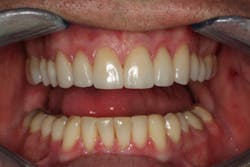

The delivery of our final restorations should be the easiest part of the treatment. By the time the delivery date arrives, we have already diagnosed and treated any functional issues as well as tested our treatment plan in the provisionals. As long as the laboratory has copied our blueprint, this should be a stress-free appointment, and we should be confident in the restorations that we’re delivering.

Through working with Darren, we were able to provide the necessary treatment to obtain the five requirements of occlusal stability. He now has stable stops on all teeth, anterior guidance in harmony with the envelope of function, anterior teeth that provide immediate posterior disclusion in protrusive, and he no longer has working and balancing side excursive interferences.

Overall, the case closely followed our treatment plan blueprint because of proper diagnosis and planning. Darren was comfortable with his envelope of function, occlusal stability was restored, and he was thrilled with his natural, esthetically pleasing smile.